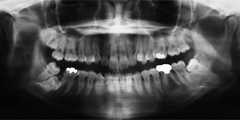

4.骨が再生されたのを確認し、インプラント治療

3.骨がくっついている6ケ月の間に全体の咬合改善(全体に被せ物をし、高さを上げる)

4.6ケ月後、骨とインプラントが完全にくっつき馴染んでから2次手術にて被せ物を入れる(インプラント治療完了)

隣接する歯と違和感がないようにもともとあった「着色」「光沢」「色合い」を合わせて被せ物を作成したため、歯が見えた時に、まったくご自分のもともとの歯として感じられます。

被せ物は決して白いだけのものがいいのではなく、あくまでも「その患者さまにとって自然にみえる」ということが大切なことです。あえて、歯茎周辺に茶色い着色を入れているのもそのためです。